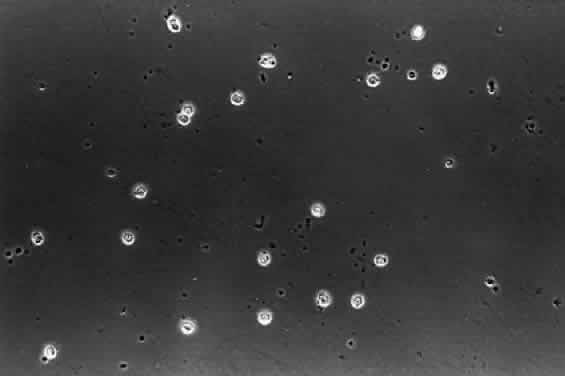

HYALOCYTES.

There are cells embedded within the posterior vitreous cortex (Fig. 18) known as hyalocytes. Situated 20 to 50 μm from the ILL of the retina, these mononuclear cells are widely spread apart in a single layer (Fig. 19). The highest density of hyalocytes is in the region of the vitreous base, followed by the posterior pole, with the lowest density at the equator. Derived from circulating monocytes and renewed every 6 months, hyalocytes are oval or spindle-shaped and are 10 to 15 μm in diameter. They contain a lobulated nucleus, a well-developed Golgi complex, smooth and rough endoplasmic reticula, many large periodic acid-Schiff-positive lysosomal granules, and phagosomes (Fig. 20). Balazs72 noted that hyalocytes are located in the region of highest HA concentration and suggested that these cells may be responsible for vitreous HA synthesis, which may also be true of vitreous collagen.

Fig. 19. Human hyalocytes in situ. Phase-contrast microscopy of flat-mount preparation of posterior vitreous cortex from the eye of an 11-year-old girl obtained at autopsy (courtesy of New England Eye Bank, Boston, MA). No stains or dyes were used in this preparation. Mononuclear cells are distributed in a single layer within the vitreous cortex (7times;115).

Fig. 20. Ultrastructure of human hyalocyte. A mononuclear cell is seen embedded within the dense collagen fibril (black C) network of the vitreous cortex. There is a lobulated nucleus (N) with a dense marginal chromatin (white C). In the cytoplasm, there are mithochondria (M), dense granules (arrows), vacuoles (V), and microvilli (Mi). (×11,670.) (Courtesy of Joe Craft and Dan Albert, MD)